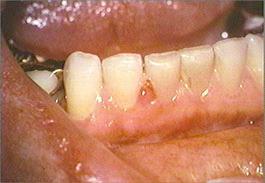

The skin on the right side of the face is erythematous and contains small vesicles and ulcers. Small ulcers are present on the right dorsum of the tongue, mucobuccal fold and the gingival papilla between the mandibular right central and lateral incisors. The mandibular right first and second molars and the surrounding mucosa are painful to palpation. The periapical radiograph reveals no evidence of periapical disease. The mandibular right first and second molars are responsive to pulp testing and give no evidence of pulpitis. No palpable lymph nodes are present.

mandibular anterior teeth and gingiva right mandibular teeth and mucobuccal fold